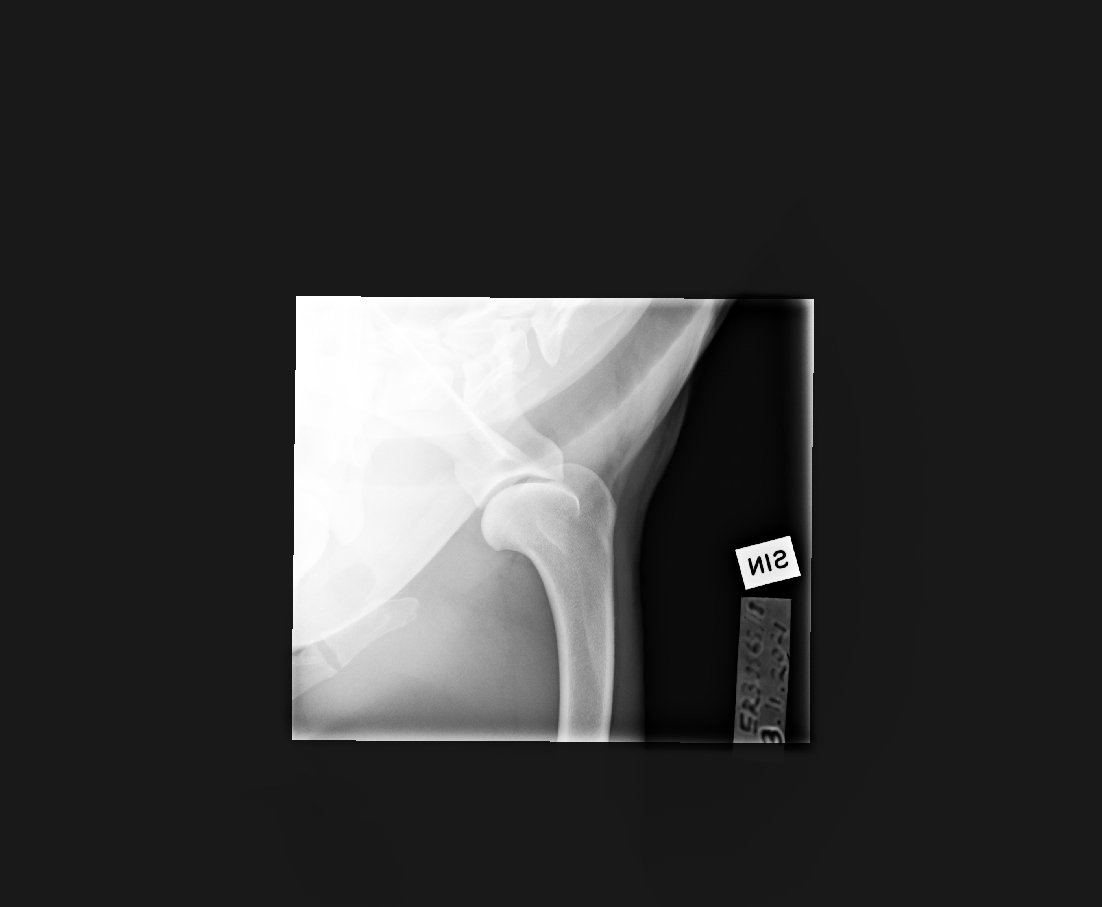

Kyynärpäät

0/0

(vasen rajatapaus)

Olkapäät (11/21):

vasen terve,

oikea tulkinnanvarainen